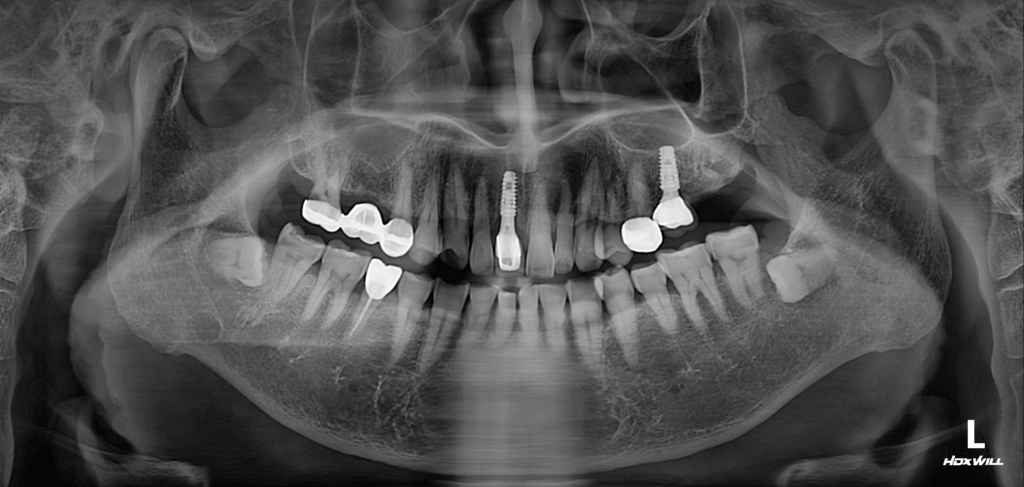

24.10.24

술전 사진

환자분께서는 우측 상악 부위의 불편감으로 영도치과 서울화이트S치과를 방문해주셨습니다.

기존에 사용하던 브릿지가 10년 이상 경과하면서 가장 뒤쪽 대구치인 #17 부위 아래쪽에서 뼈가 많이 줄어든 상태가 확인되었습니다.

이로 인해 임플란트를 안정적으로 식립하기 위해서는 먼저 골높이를 확보하는 골이식 과정이 필수적이었고, 어떤 방식의 골이식이 적합한지 판단해야 했습니다.

정밀 검사 결과, 저희 영도치과 서울화이트S치과에서 Crestal 접근의 기준으로 삼는 약 5mm 수준의 잔존골이 확보되어 있었기 때문에 이 방법으로도 충분히 임플란트가 가능하다고 결론 내렸습니다. 이에 따라 Crestal 골이식 방식을 적용해 골을 보강한 뒤 임플란트 식립까지 무리 없이 진행하였습니다.